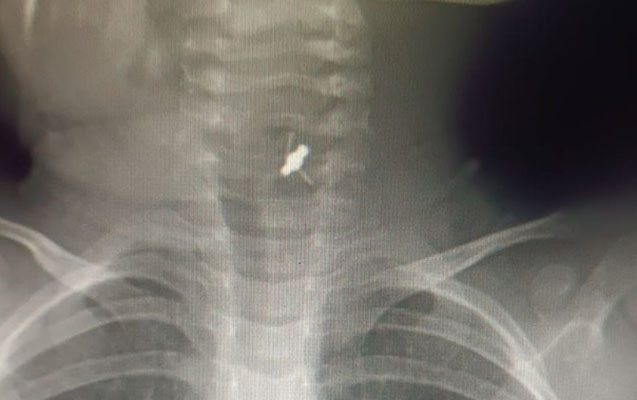

Həkim bildirib ki, azyaşlı tibb müəssisəsinə tənəffüs çatışmazlığı və boğulma şikayətləri ilə gətirilib:

“Aparılan müayinələr əsasında xəstənin yad cisim udduğu məlum olub. Xəstəyə bronxoskopiya icra edilərək baş bronx mənfəzindən yad cisim-saç sancağı xaric edilib”.